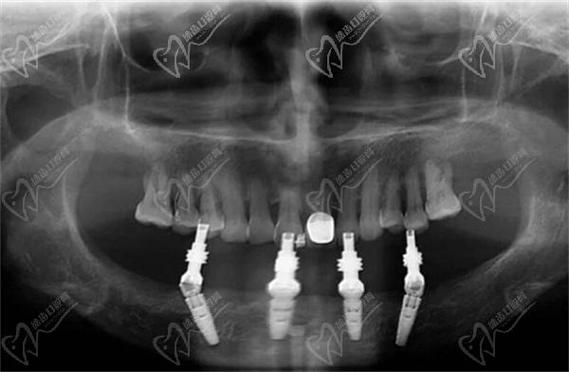

基台安装与临时桥修复:植入种植体后,安装愈合基台,取模制作临时固定桥,术中即刻佩戴,植牙图中会标注临时桥的咬合调整要点(如正中咬合无早接触、前牙引导无干扰)。

永久修复:骨结合完成后,更换愈合基台为永久基台,取模制作全瓷固定桥,试戴调整咬合后粘固,植牙图中会展示永久桥的边缘密合度、邻接关系及抛光效果。